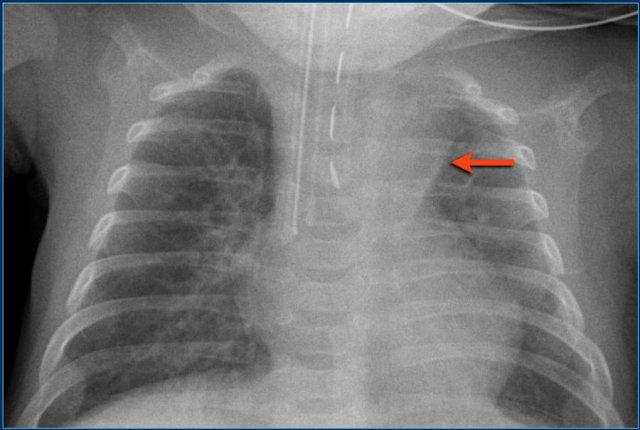

PICC line (3)

Các phát hiện bao gồm:

- PICC line đặt lạc chỗ.

Có thể nằm trong xoang vành hoặc trong nhĩ trái sau khi đi qua lỗ bầu dục còn thông.